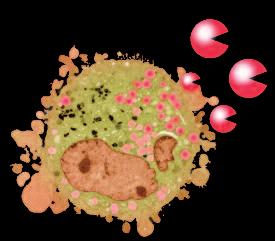

La pagina a fianco mostra l'immagine di una cellula tumorale reale, visualizzata al microscopio elettronico, che ingrandisce questa cellula 6500 volte rispetto alle sue normali dimensioni. Questo tipo di cellula prende il nome di carcinoma, cioè derivante da cellule epiteliali, il tipo di cellule che rivestono sia le superfici interne (polmoni, intestini) che esterne (pelle) del corpo.

Grazie a questo ingrandimento si possono identificare chiaramente alcune delle caratteristiche di tutte le cellule tumorali: a) l'enorme nucleo cellulare dalla forma insolita che spiega la loro grande capacità di riprodursi e b) la struttura non uniforme, complessa della superficie cellulare, che riflette una forte attività di secrezione di sostanze prodotte dalle cellule tumorali.

Una delle più importanti molecole secrete dalle cellule tumorali in grandi quantità sono gli enzimi a ‘forbice’ che digeriscono il collagene. Sono aggiunti graficamente a questa immagine, sotto forma di strutture simili ad un ‘pacman’ rosso.

“Forbici biologiche” – Enzimi

Naturalmente questi sfere, nella vita reale, sono molecole biologiche, proteine, che hanno la capacità di tagliare le fibre di collagene e di altre molecole del tessuto connettivo. L‘immagine sopra mostra che non c’è un solo tipo di 'pacman' ovvero di queste molecole, ma

Digestione del tessut o connet tivo del tessuto connetti vo diversi tipi, quali il plasminogeno/plasmina e le metalloproteasi (strutture colorate tridimensionali). Queste molecole migliorano il loro effetto distruttivo attivandosi reciprocamente in forma di reazione a catena in cascata.

La foto nella pagina a fianco mostra una cellula cancerogena ad un microscopio.

Il corpo di questa cellula tumorale in migrazione si espande nella direzione del suo movimento all’interno del tessuto. Può formare una struttura ‘tentacolare’ che trascina la cellula tumorale lungo la superficie, in questo caso, di un vaso sanguigno.

Gli enzimi che digeriscono il collagene sono aggiunti per illustrare il processo mediante il quale qualsiasi ostacolo sul cammino di questa cellula tumorale viene superato.